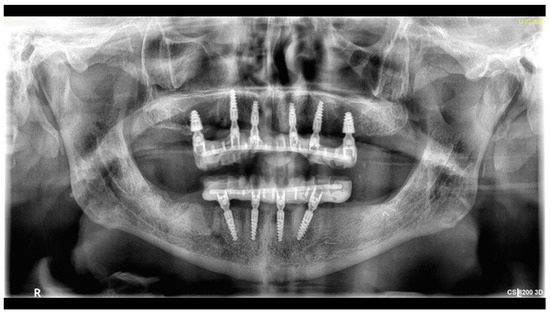

- One-day surgery with implant placement, MUA, and intraoral welding to obtain immediately loaded long-lasting temporaries.

- The conduction of an analogue impression, an I.O. scan, a removable 360° scan, and a scanflag scan.

- The conduction of a Sheffield passive fit test of 3D-printed try-ins on a milled titanium bar.